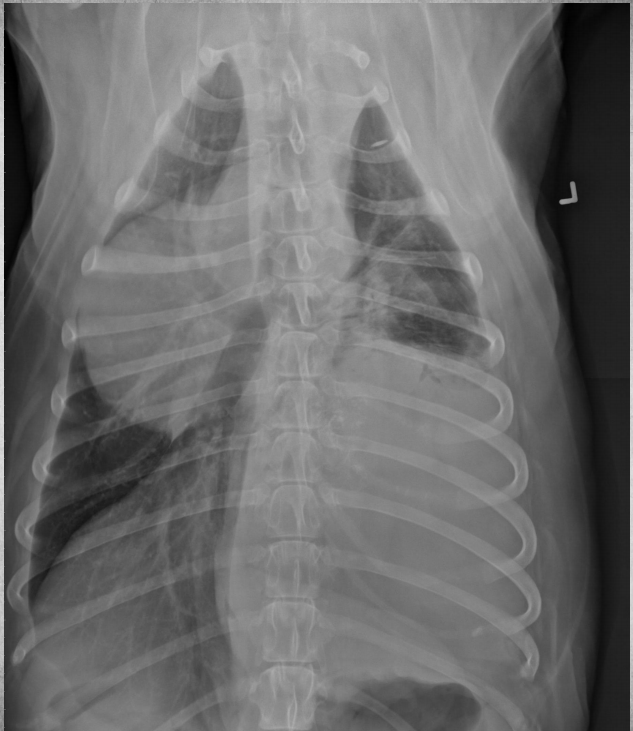

● 7 yo castrated male Golden

Retriever

● Lethargy for last 24h

fat along cranioventral aspect of thorax, maybe fluid too at heart apex.

pericardial effusion: very round heart margin tells you its fluid and not just cardiomegaly.

mild bronchial pattern